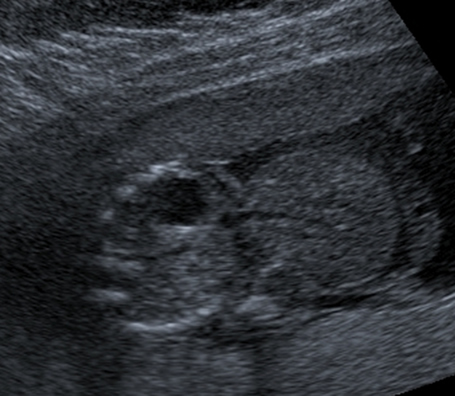

An abdominal wall defect is an abnormal type of hernia either through the cord insertion or by the side of the cord. In this ultrasound image, note the outline of the herniated contents outside the abdomen. The fetal spine and fetal stomach can also be seen.